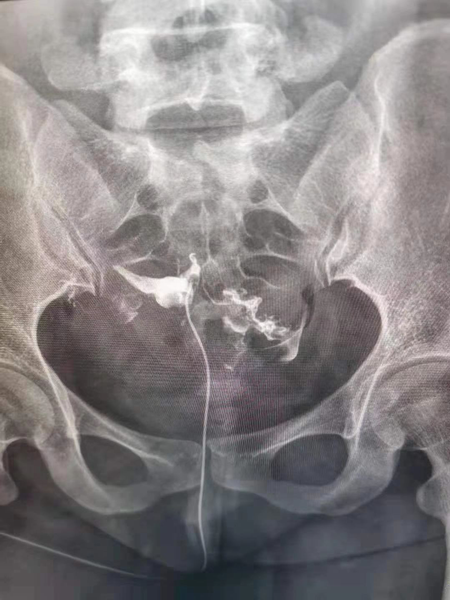

1.造影成像的圖像質量清晰直觀,臨床醫生可以通過讀片來判斷子宮輸卵管腔內的狀態,清晰的圖片對于炎癥、積水等異常診斷更為準確,降低了漏診率和誤診率,對下一步不孕癥的處理方向提高幫助。

2.診斷同起到治療作用,輸卵管內的炎癥碎片、粘液栓、細小的纖維絲均可引起輸卵管的閉塞,并且輸卵管腔內有復雜的皺襞樣結構,造影劑在通過輸卵管腔時,可通過沖刷疏通的作用,改善輸卵管腔內的粘連堵塞,為精子和卵子的運送提供暢通的道路,還可以恢復腔內纖毛的活動,為運送受精卵做好準備。